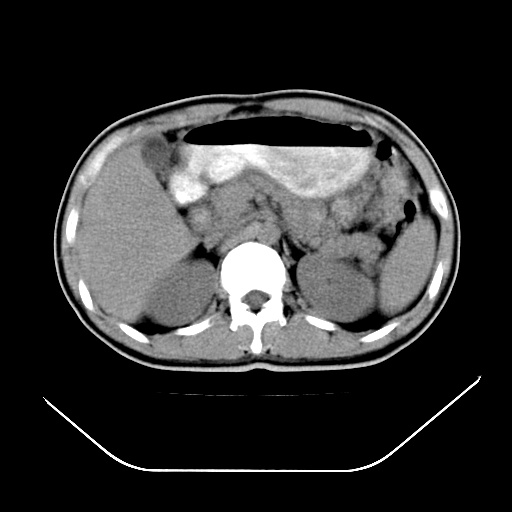

以下是引用深泽交通医院在2008-7-17 12:05:00的发言:[br]肝门淋巴结肿大;胆结石

以下是引用随光逐影在2008-7-17 17:52:00的发言:[br]1)胆囊结石。2)肝门及胰头区淋巴结肿大可能(原因不明);建议行进一步检查。

以下是引用卜一在2008-7-17 16:37:00的发言:[br]支持胆囊结石!!!至于胰头区病变——建议强化后再定论!